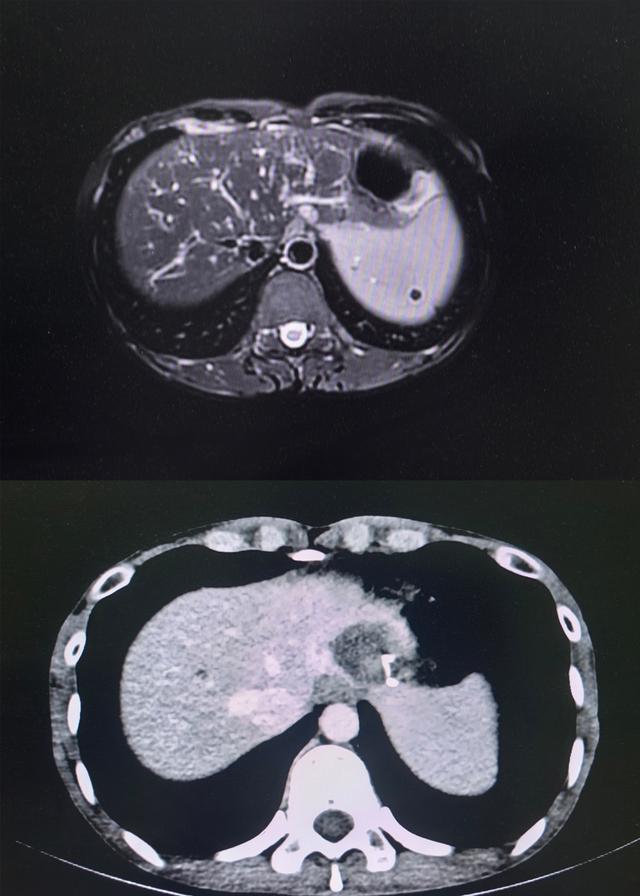

术前术后影像资料对比

术后即时造影确认,患者肿瘤组织被完整消融,毗邻重要器官结构毫发无损,术后增强CT扫描及三维重建检查进一步证实,肿瘤已实现完整消融,手术取得圆满成功。